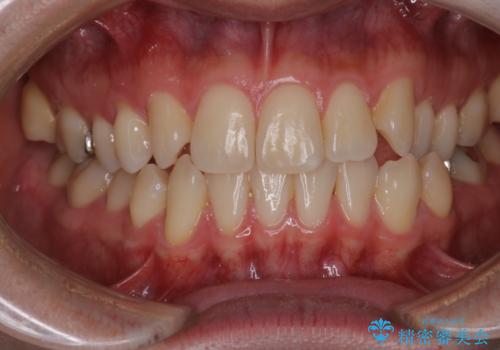

- 右上2番が欠損しており、歯並びをバランスよくしたいということで来院されました。

ワイヤー装置とマウスピースで悩まれていましたが、マウスピースで治療可能と判断致しましたのでマウスピースにて治療しました。

IPR、歯列弓拡大、ゴム掛けを行い歯並びを整える治療計画を立てました。

右上2番が欠損しているため、見た目と噛み合わせの両方のバランスを整えるために経過を追いながら必要な部位にゴム掛けをしました。

最終的に、見た目も噛み合わせも患者様に満足いただけました。